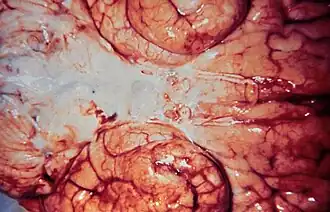

La meningitis puede ser diagnosticada post mortem. Los hallazgos de la autopsia por lo general consisten en una inflamación generalizada de la piamadre y la aracnoides. Los neutrófilos suelen haber migrado al LCR y la base del cerebro, junto con los pares craneales y la médula espinal, pueden estar rodeados de pus, al igual que los vasos meníngeos.[42]

En el examen macroscópico de material de autopsia obtenido de un paciente muerto por meningitis purulenta se observa el encéfalo tumefacto, los vasos sanguíneos ingurgitados y el espacio leptomeníngeo con exudado purulento, en particular en la convexidad. Cuando el exudado no es muy abundante se lo halla sobre todo junto a los vasos, a lo largo de los cuales se extiende en forma de delgadas bandas amarillentas. El exudado también tiende a acumularse en las cisternas y cuando es abundante forma una capa continua en el espacio subaracnoideo. Lo habitual es que también se lo halle en el sistema ventricular.[43] El exudado está compuesto fundamentalmente por células polinucleares con cantidad variable de fibrina. Si no se reabsorbe en la primera semana, en la segunda aparecerán linfocitos y células plasmáticas y en la tercera habrá tejido granulatorio.[43]

En la necropsia de los pacientes que han muerto por meningitis bacteriana se observa un exudado purulento que cubre la corteza cerebral y que es más abundante en los surcos, en la base del cerebro y en la médula espinal; también hay edema cerebral, infiltrado de leucocitos polimorfonucleares en las leptomeninges y dilatación y trombosis de los capilares, las vénulas y los vasos mayores.